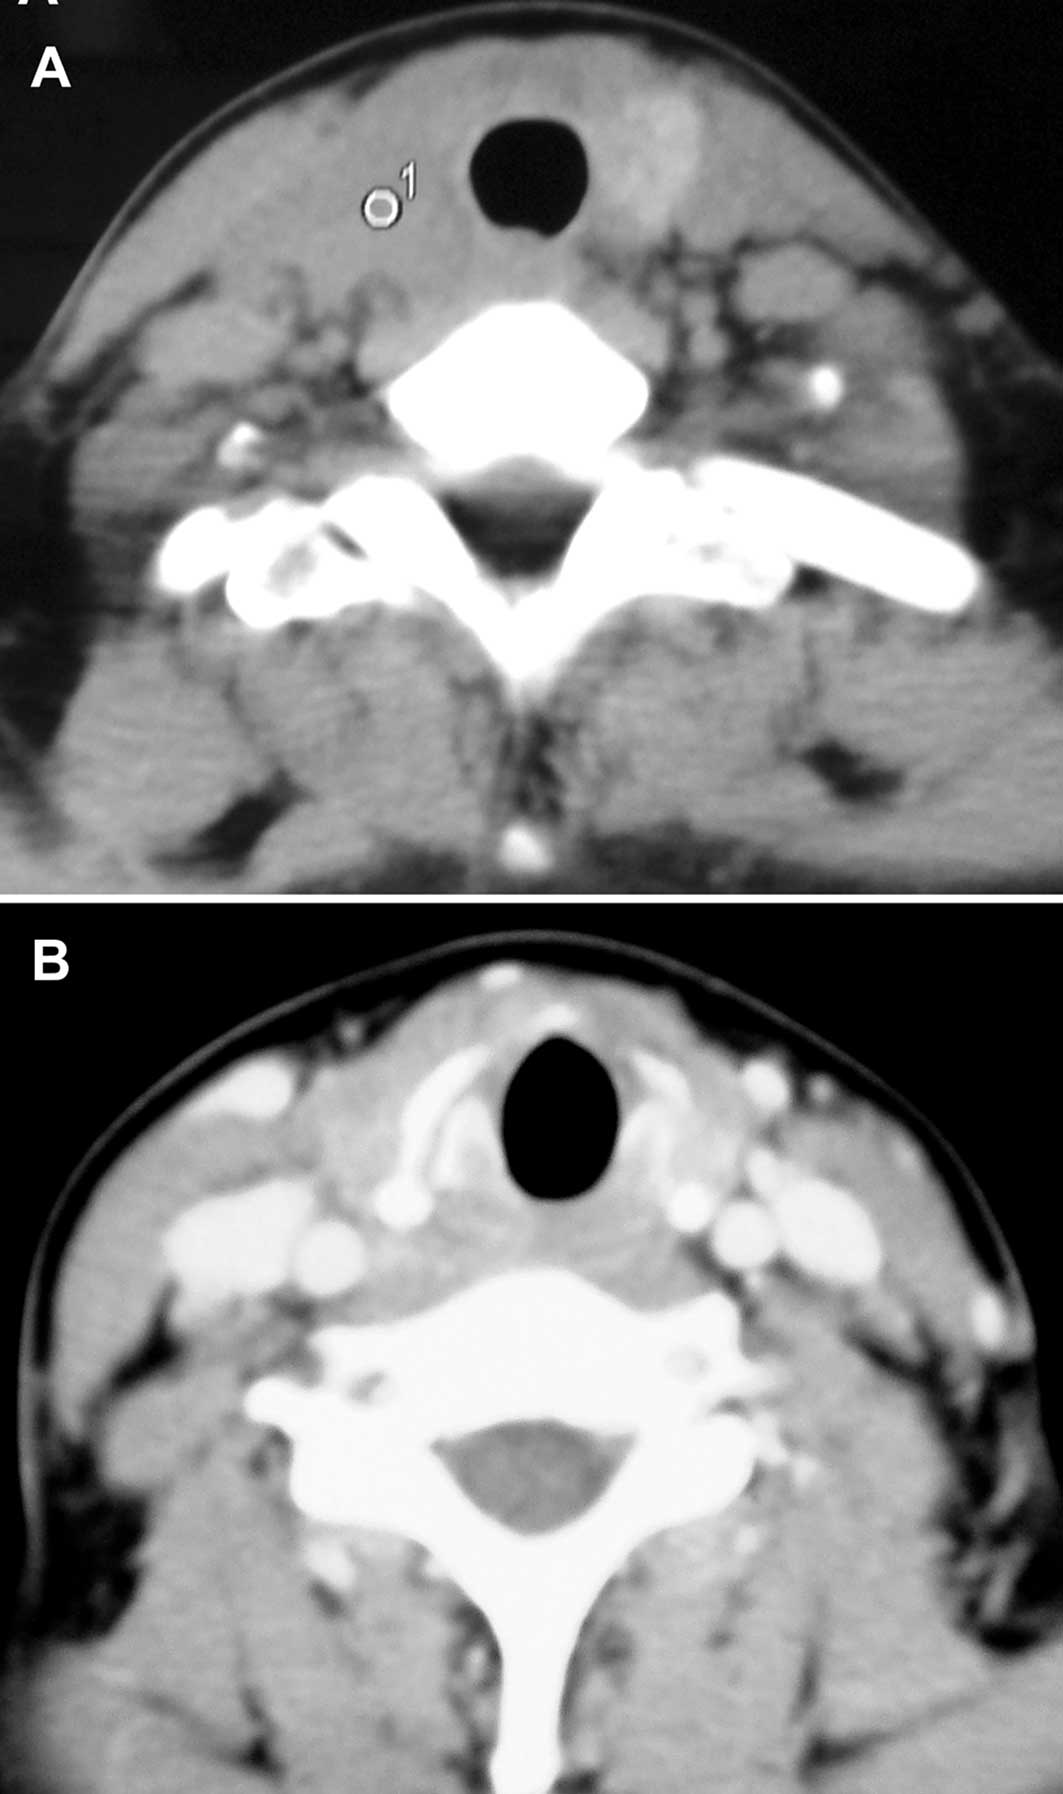

A CT scan (Fig. 1) revealed that a 39-year-old Chinese female had a 3.3 cm solid mass in her thyroid, mainly located in the right lobe with bilateral cervical lymph node enlargement, in March 10, 2010. This occurred 21 months following total resection of the right parotid gland. In June 2008, the patient had undergone surgery on the right salivary gland tumor, pathologically diagnosed as ‘the basal cell adenocarcinoma’. The patient then received local 125I radioactive bead implantation one month after the operation. Approximately 12 months later, a soybean-sized tumor appeared on her neck, followed by dysphagia and hoarseness with thyroid enlargement. A neck CT examination was performed in March 10, 2010, showing the thyroid gland and right cervical lymph node enlargement, with no abnormality in the parotid region. A bilateral neck dissection with a total right and partial left thyroidectomy were concomitantly performed. An intraoperative dissection showed the bilateral cervical lymph nodes and thyroid glands to be involved, with the former being swollen, solid and showing invasion into the surrounding tissue, and the latter, particularly the right lobe, having an indefinite boundary with the surrounding tissue. A myoepithelial carcinoma was pathologically diagnosed in the lymph nodes and thyroid postoperatively. Full consent was obtained by the patient.

Figure 1

The CT scan showed a thyroid mass.